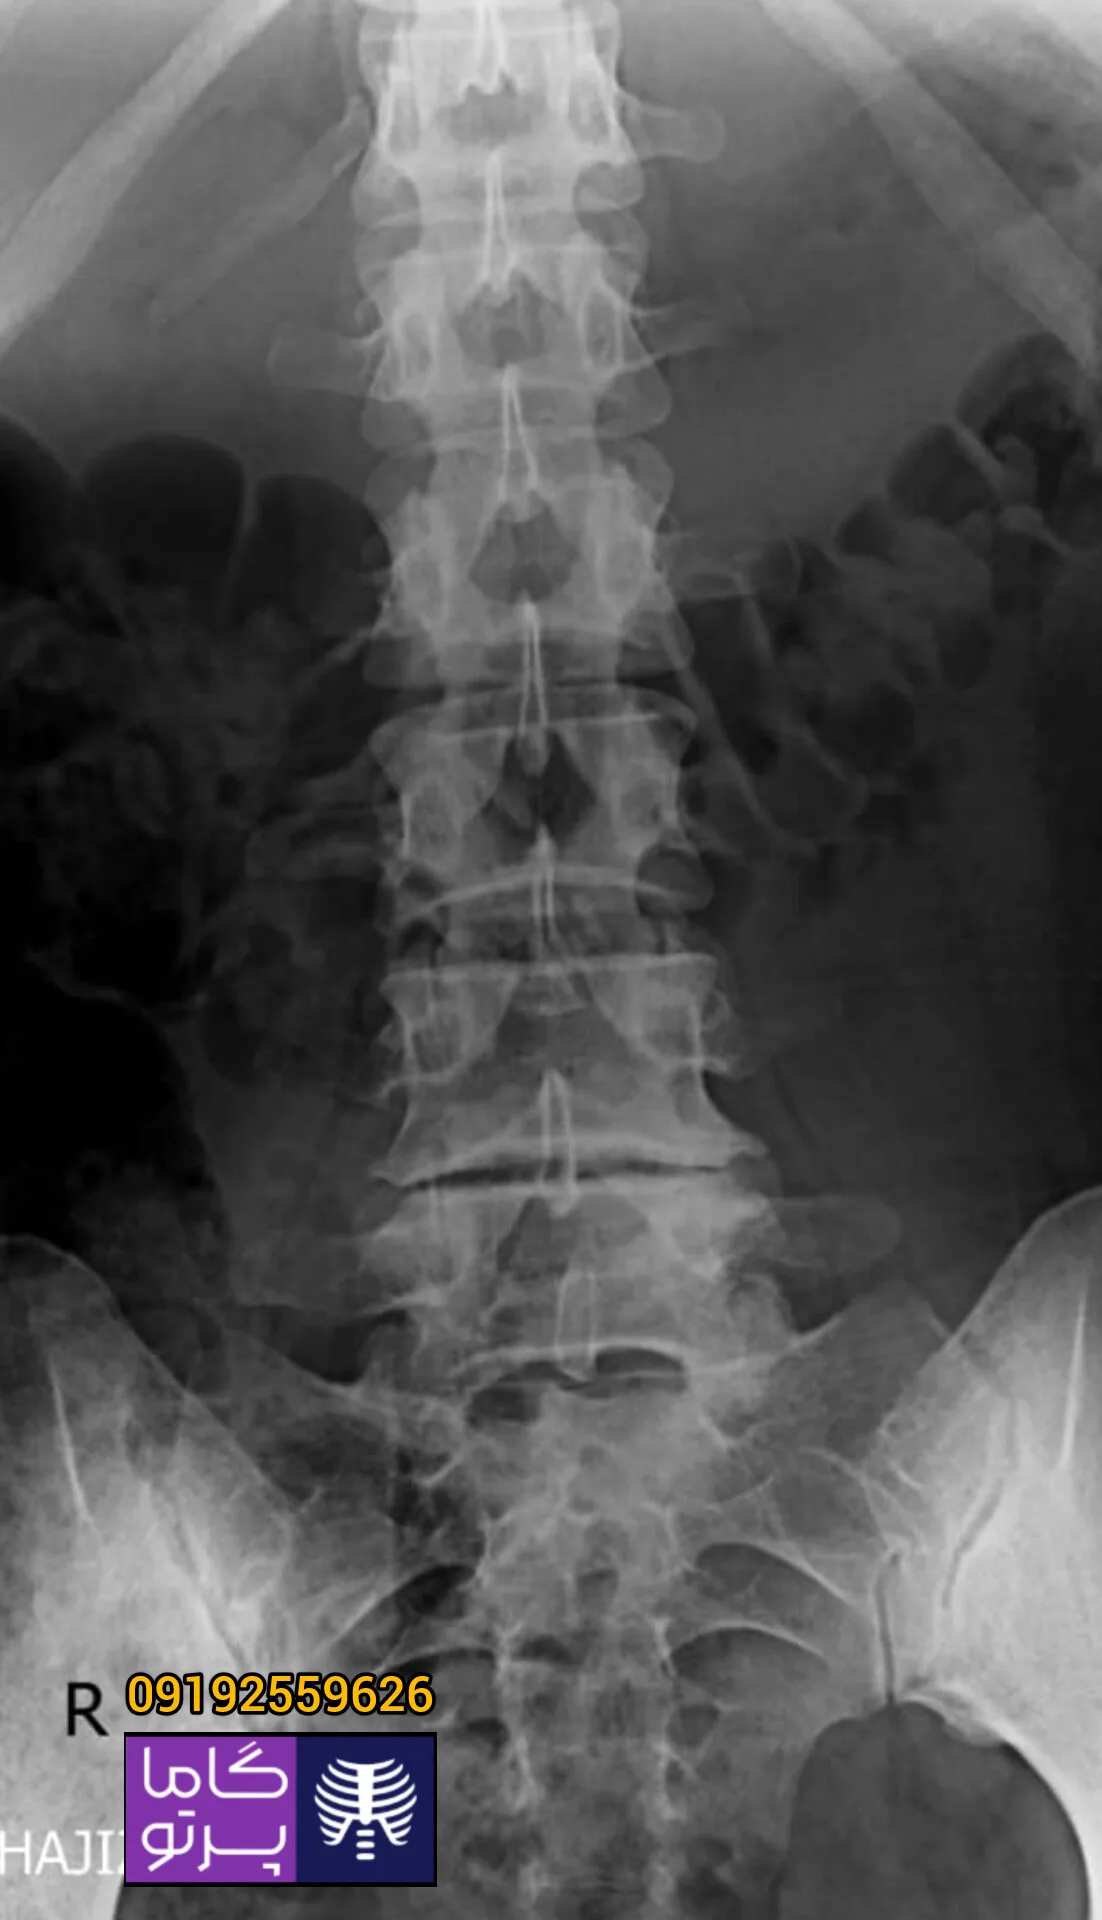

تصاویری از رادیولوژی در منزل توسط گاما پرتو

در این روش تصویر برداری یک صفحه (گیرنده یا دتکتور) در زیر عضو و قسمت مورد نظر قرار داده می شود و اشعه ایکس(دُز از اشعه جهت تشخیص) به همان قسمت که روی صفحه قرار گرفته تابنده می شود و توسط صفحه اطلاعات دریافت می شوند و همین اطلاعات پس از پردازش های لازم در نهایت عکس رادیولوژی به ما ارائه می دهد. کاربردهای رادیولوژی در منزل دقیقاً همان کاربرد رادیولوژی در بیمارستان ها می باشد از جمله بررسی انواع شکستگی ها، دررفتگی مفاصل، آرتروز مفاصل، دیدن پروتز های داخل استخوان از نظر بررسی موقعیت پروتز، آب آوردگی ریه(اِدم وافیوژن) و عفونت ریه، شکستگی دنده ها، انساد و وجود هوا در شکم و… می باشند. رادیولوژی در منزل تمام این خدمات را ارائه می دهد.